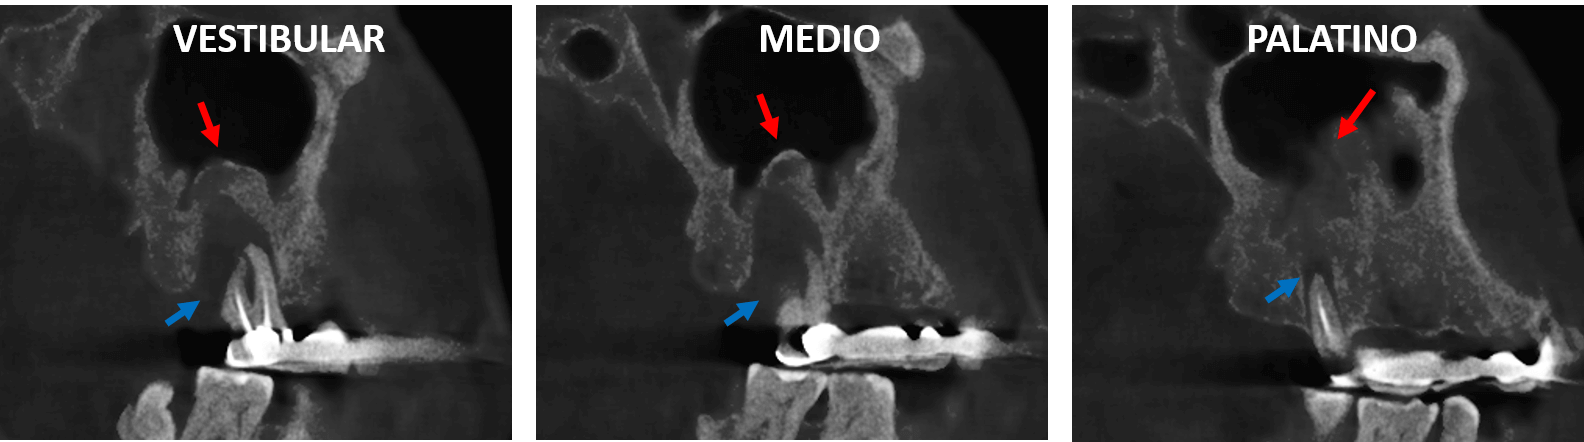

Fig.2

En cortes axiales (Fig.2) se observa la lesion osteolítica pararradicular amplia comprometiendo casi la totalidad del soporte óseo dentario y se evidencia la ausencia de obturación en un segundo conducto mesiovestibular.